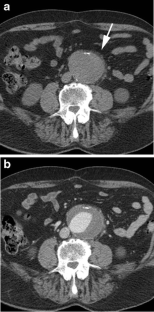

Fig. 2